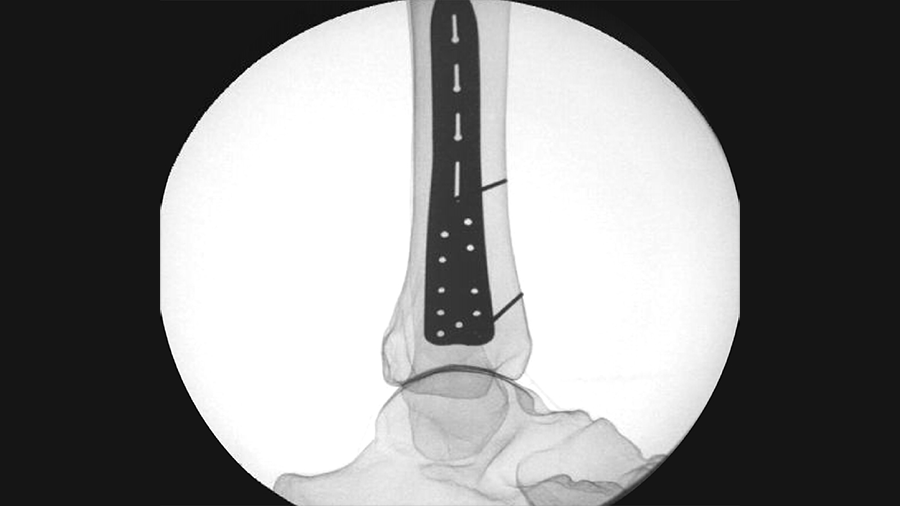

New Templates for USF System

The widely used Universal Small Fragment System has been expanded to meet clinical needs.